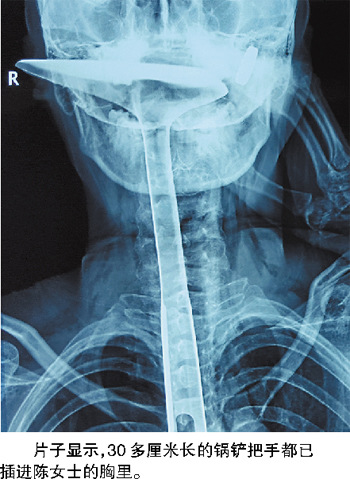

陈女士被紧急送到医院,当晚又被转送到康华医院。在医院拍的片子显示,30多厘米长的锅铲把手都已插进陈女士的胸里,情况非常危急。记者从医生手机里保存的照片上看到,当时陈女士的嘴巴张着,只有锅铲的前端还露在嘴巴外面,她的左手扶着锅铲,锅铲上和手上都是血。

觉得喉咙很痒、很堵,家住虎门的陈女士就用炒菜的锅铲的把手去捅喉咙里的“大疱”,结果30多厘米长的铝合金锅铲把手捅进去就拔不出来了!陈女士被紧急送到医院,经过两次手术后,锅铲把手被取出,但她因此损失了20厘米的食道,原约25厘米长的食道只剩下了5厘米。